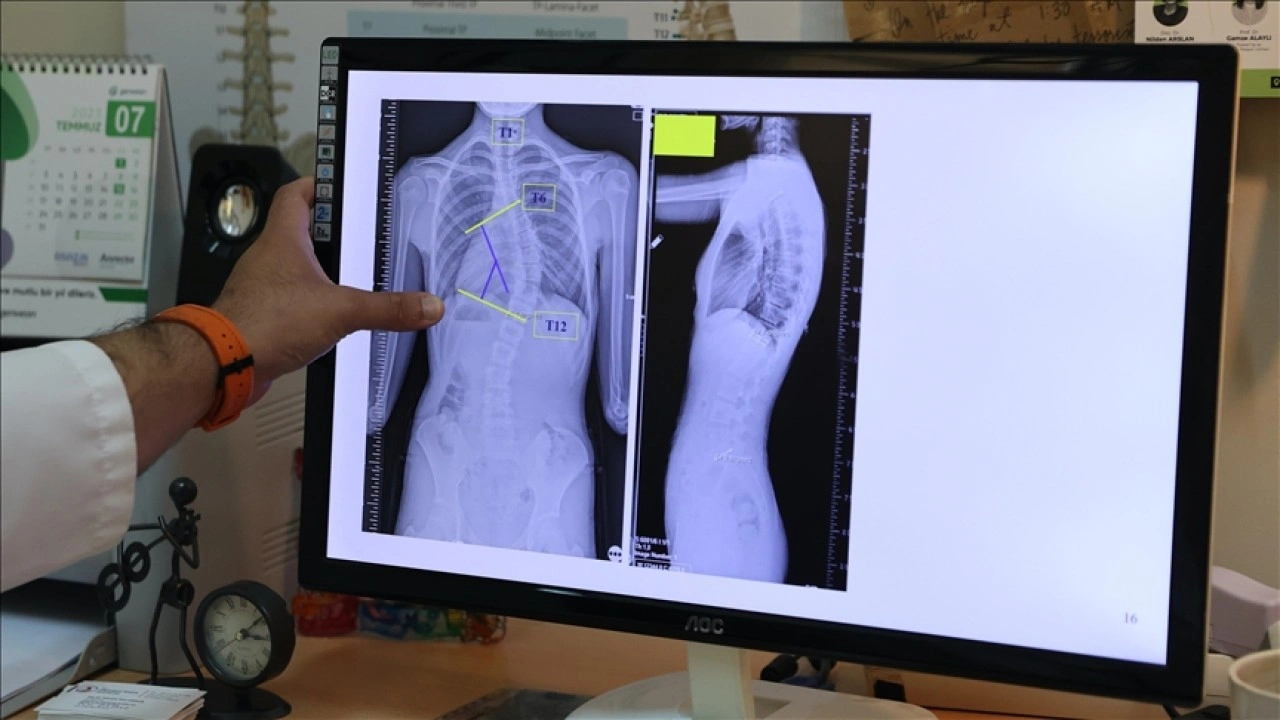

Başaran, yaptığı yazılı açıklamada, skolyozun omurganın üç boyutlu düzlemde sağa ya da sola eğrilmesi anlamına geldiğini, omurgada S veya C şeklindeki bu eğilmelerin yüzde 80'inin nedeninin bilinmediğini aktardı.

"Toplumda 10 dereceye kadar olan omurga eğriliklerine çok sık rastlıyoruz. Bunları normal, postürel eğrilikler olarak tanımlıyoruz. 10 dereceyi geçen eğriliklerde skolyoz hastalığı tanısı koyuyoruz. 20 dereceye kadar olan eğrilikleri 6 aylık aralıklarla büyüme dönemlerine göre takip ediyoruz. 20 dereceyi geçen eğriliklerde ise çocukları egzersiz programına alıyoruz ya da çeşitli korselerle hastalığının ilerlemesini engellemeye çalışıyoruz."

Çocukların hızlı büyüdüğü dönemde önerdikleri korse ve egzersizin, aslında skolyozu iyileştirmeye yönelik tedaviler olmadığını, burada cerrahi sınıra yaklaşmadan hastalığı durdurabilmeyi amaçladıklarını ifade eden Başaran, erişkinlik döneminde 40 dereceyi aşan omurga eğriliğinde cerrahi tedavi önerdiklerini aktardı.